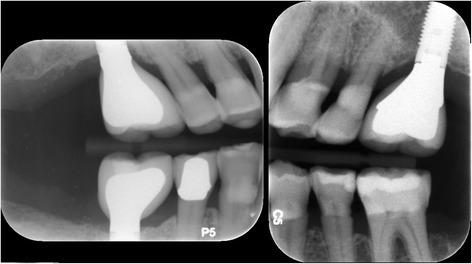

Patients with resorbed edentulous alveolar ridges in the posterior maxilla often require lateral window sinus augmentation procedures prior to implant placement. Lateral window sinus augmentation procedures can produce incomplete bone augmentation as consequence of surgical and healing complications producing unusual and complex sinus anatomy. Although incomplete bone formation after sinus augmentation has been described in a previous case reports, this is the first case report that describes grafting these compromised sites prior to implant placement.

A 65-year-old male patient with no known medical conditions presented with severe chronic localized periodontitis and a combined periodontal-endodontic lesion affecting three first molars. Initial ridge preservation and lateral window sinus augmentation resulted in incomplete bone formation and complex sinus floor anatomy on both right and left sides. A dilating balloon technique on one side and a palatal approach on the other side were utilized for additional sinus augmentation using particulate allograft and resorbable collagen membranes. Healing was uneventful, and implants could be placed and restored at all sites. Periodontal maintenance was conducted every 3 months, and the implants have been in function and periodontally healthy for 2 years.